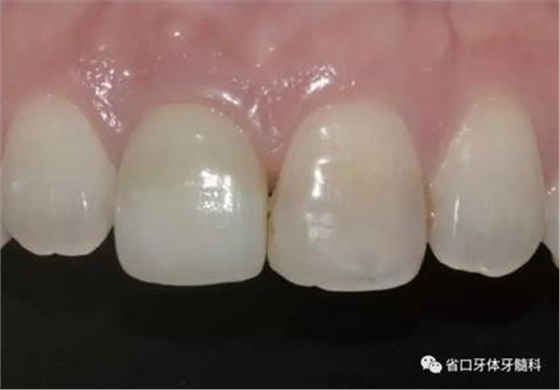

(3)術(shù)后醫(yī)囑與牙齦塑形:術(shù)后予以抗炎止痛對癥處理,7~10天拆 線。術(shù)后3個月開始逐步調(diào)整臨時冠并塑形牙齦形態(tài),控制上頜右側(cè)中切牙 近遠(yuǎn)中牙齦乳頭的充盈量和齦緣水平,使得上頜右側(cè)中切牙牙齦形態(tài)與上頜 左側(cè)中切牙盡量相對稱。

圖25 術(shù)后3個月

圖26 牙齦塑形

圖27 牙齦塑形

圖28 牙齦塑形

圖29 牙齦塑形

(4)最終修復(fù)與隨訪:經(jīng)過3個月左右的塑形,上頜右側(cè)中切牙臨時修復(fù)固位良好,菌斑控制良好,近遠(yuǎn)中齦乳頭充盈良好,齦緣水平及形態(tài)與 鄰牙相對稱。牙齦塑形穩(wěn)定后,以臨時修復(fù)體制作個性化轉(zhuǎn)移桿并取模轉(zhuǎn)移,并以原廠氧化鋯基臺制備個性化基臺及全瓷冠。正確就位最終基臺,加 力30N·cm。制備粘接代型,去除多余粘接劑,以Unicem粘接固位上頜右側(cè)中切牙全瓷修復(fù)體。固化穩(wěn)定后,再次確定咬合無干擾。最終修復(fù)完成后 隨訪3個月及6個月,上頜右側(cè)中切牙種植修復(fù)固位穩(wěn)定,近遠(yuǎn)中齦乳頭充 盈良好,唇側(cè)齦緣水平穩(wěn)定。